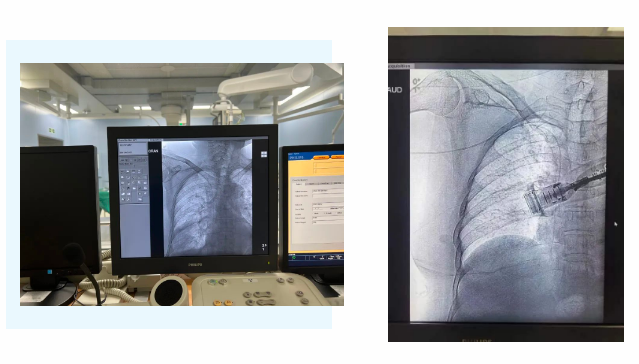

在麻醉手術中心的配合下,手術首先由韓海靜護士長在超聲引導下應用“塞丁格”法穿刺將針尖一樣細的導絲送入血管,術中在DSA透視下將導管沿著血管送達上腔靜脈,尖端精準定位至上腔靜脈開口處。隨后,胸腔外科支亞男主治醫(yī)師在穿刺點下方取2厘米小切口內進行上臂港囊袋和隧道的制作及導管與港座連接,最后進行港體埋植及皮內縫合,使患者切口隱蔽美觀創(chuàng)傷小,術中出血量極少。手術在X片影像留影,最終手術順利完成。